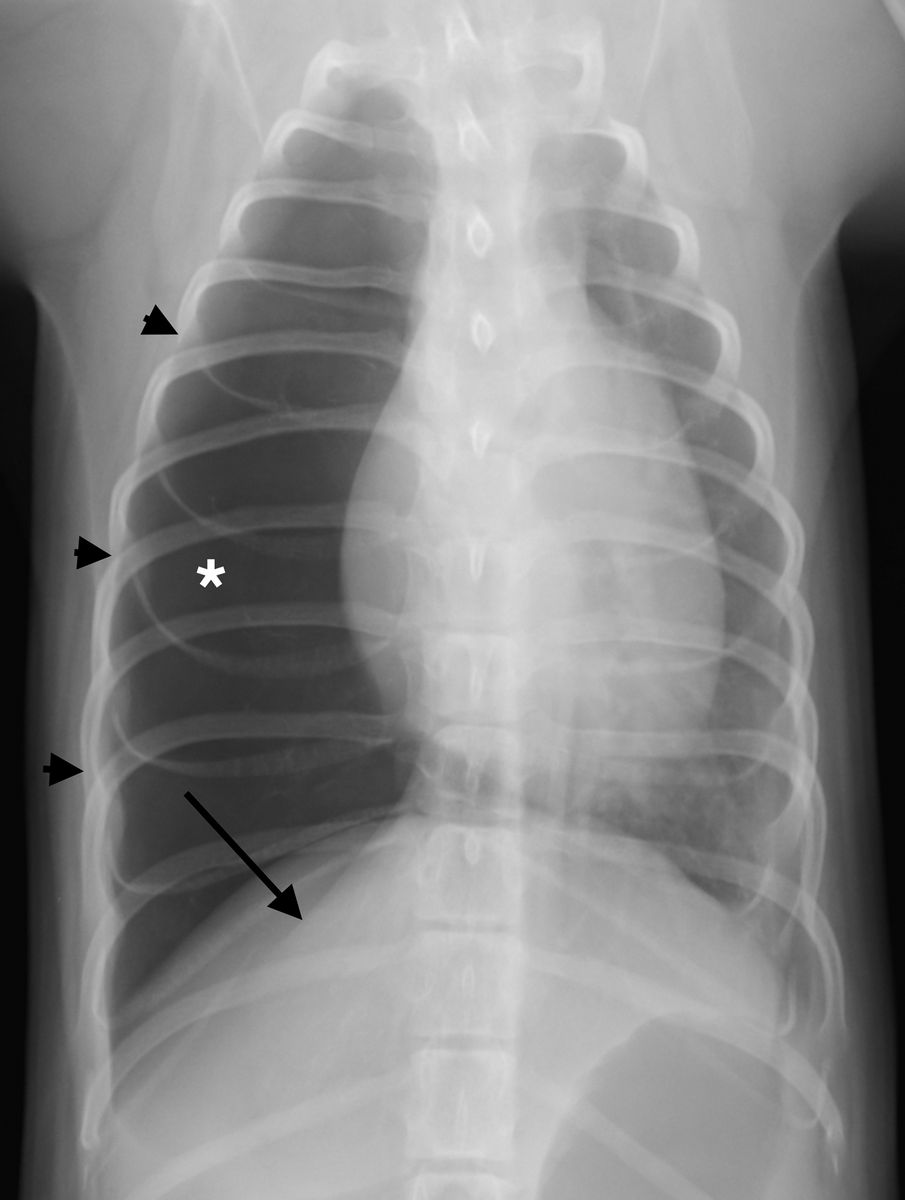

Dorsoventral radiograph of the thorax of a dog with congenital lobar emphysema (CLE) of the right middle lung lobe. Note the enlarged and hyperlucent lung lobe (*), expanded right side of the rib cage (black arrowheads) and compressed right diaphragmatic crus (black arrow). It was not possible to determine which lobe was emphysematous based on the radiographs alone